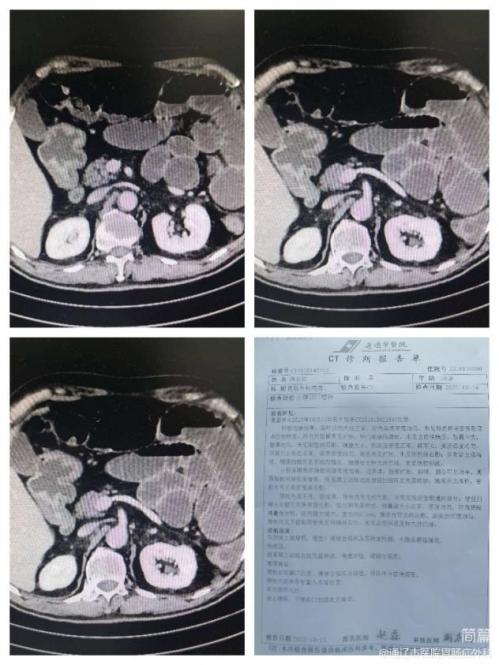

近日,我院胃肠疝外科收治了一名老年男性患者。患者主因:“腹痛原因待查”入院。既往有高血压病病史4年,最高达:205/125mmHg,冠心病病史5年,脑梗死病史6年,帕金森病病史5年。患者腹部症状重,血常规示:白细胞计数为:20.08×10^9/L。患者病情危重,急诊开通绿色通道,行腹部增强CT检查提示:肠系膜上动脉远段充盈缺损,考虑血栓形成。张国友副院长和郭云峰副主任医师积极组织科内病历讨论,诊断为肠系膜血管栓塞、肠梗阻、急性弥漫性腹膜炎、感染性休克、肠坏死。患者生命危在旦夕!我院医生向患者家属详细交代病情,说明治疗方案,建议立即急诊行腹腔探查术。手术于深夜开始,清晨结束。在张国友副院长的指导下,由郭云峰副主任医师主刀,张书法副主任医师、白力嘎医师辅助顺利完成。术中见腹腔内肠间散在脓肿形成,距回盲部约10cm远端回肠缺血坏死,长度约150cm。阑尾化脓改变。行坏死回肠切除术及阑尾切除术。术后在胃肠外科全体医护人员精心护理下,患者恢复良好,痊愈出院。

腹部CT: